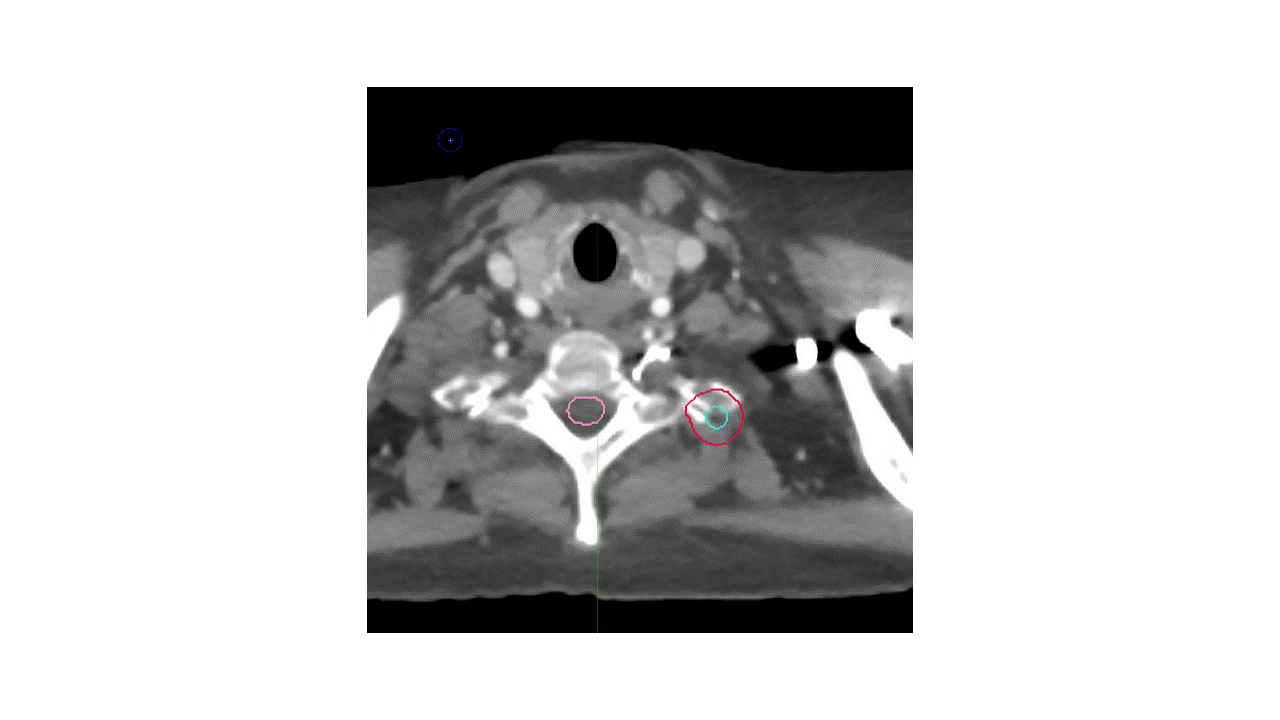

Alternative 1

Alternative 2

Which volumes are the most appropriate?

A. LUL primary tumor with margin, no LN and limited vertebral body inclusion

B. LUL primary tumor + hilar LN, with inclusion of entire vertebral body and left-sided pedicle/process/lamina

C. LUL primary tumor and limited vertebral body inclusion + hilar/mediastinal lymphadenopathy

Answer: B

There are several potential approaches to this case. Given that the mass extends into the vertebral body and the T2 neural foramen, with unclear borders, the International Spine Radiosurgery Consortium consensus guidelines were utilized, with inclusion of the ipsilateral neural foramen and vertebral body substructures. Choices A and C are too limited with respect to vertebral body coverage, and actually appear to miss gross disease. A thin-slice MRI scan was used for treatment planning and a spinal cord PRV was utilized to ensure appropriate coverage with adequate sparing of the spinal cord.

The second major question is whether to cover the left hilum and the mediastinum. Given that the EBUS was negative, it would be reasonable to omit the entire mediastinum. However, in this case, the decision was made to cover the ipsilateral hilum given the strong avidity in the left hilum and the proximity of the mass to the left hilum, this region was covered as well.